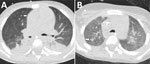

Patient 3 was a 4-year-old boy with newly diagnosed acute myeloid leukemia who initially received cytarabine-based induction chemotherapy (Table). He experienced seizures secondary to cerebral hemorrhage, requiring mechanical ventilation. After successful extubation, we resumed chemotherapy using a high-dose cytarabine and mitoxantrone regimen. He received micafungin (4 mg/kg 2×/wk) as antifungal prophylaxis. Subsequently, he experienced febrile neutropenia (temperature 39.2°C/102.6°F) that was unresponsive to empiric broad-spectrum antimicrobial treatment with meropenem and vancomycin, raising suspicion for IFD. We initiated voriconazole. Serum galactomannan test results were negative. A chest CT scan demonstrated nodular infiltrates and a new cavitary lesion radiographically consistent with a mold infection (Figure 2, panel A). We switched antifungal therapy to liposomal amphotericin B (L-AmB). Fungal culture from a tracheal aspirate yielded a mold with sterile mycelium, which we identified via ITS sequencing as B. adusta or B. fumosa (10). Other diagnostic assessments yielded no findings (Table). After 2 weeks of L-AmB therapy, the patient experienced hypokalemia, requiring a switch back to voriconazole. A follow-up CT scan performed 3 weeks later demonstrated a radiographic response to treatment (Figure 2, panel B). No further imaging was done. The patient continued voriconazole therapy for a total of 4 months.